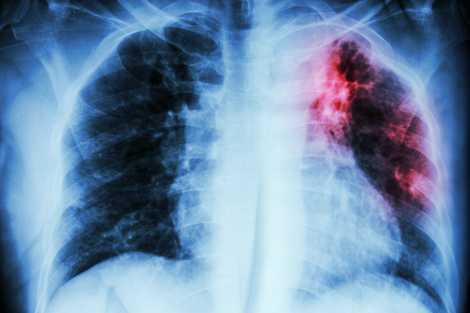

How is ILD Diagnosed

The diagnostic tests for ILD are pulmonary function tests to check the working of the lungs, imaging tests like X-rays, blood tests, and bronchoscopy.